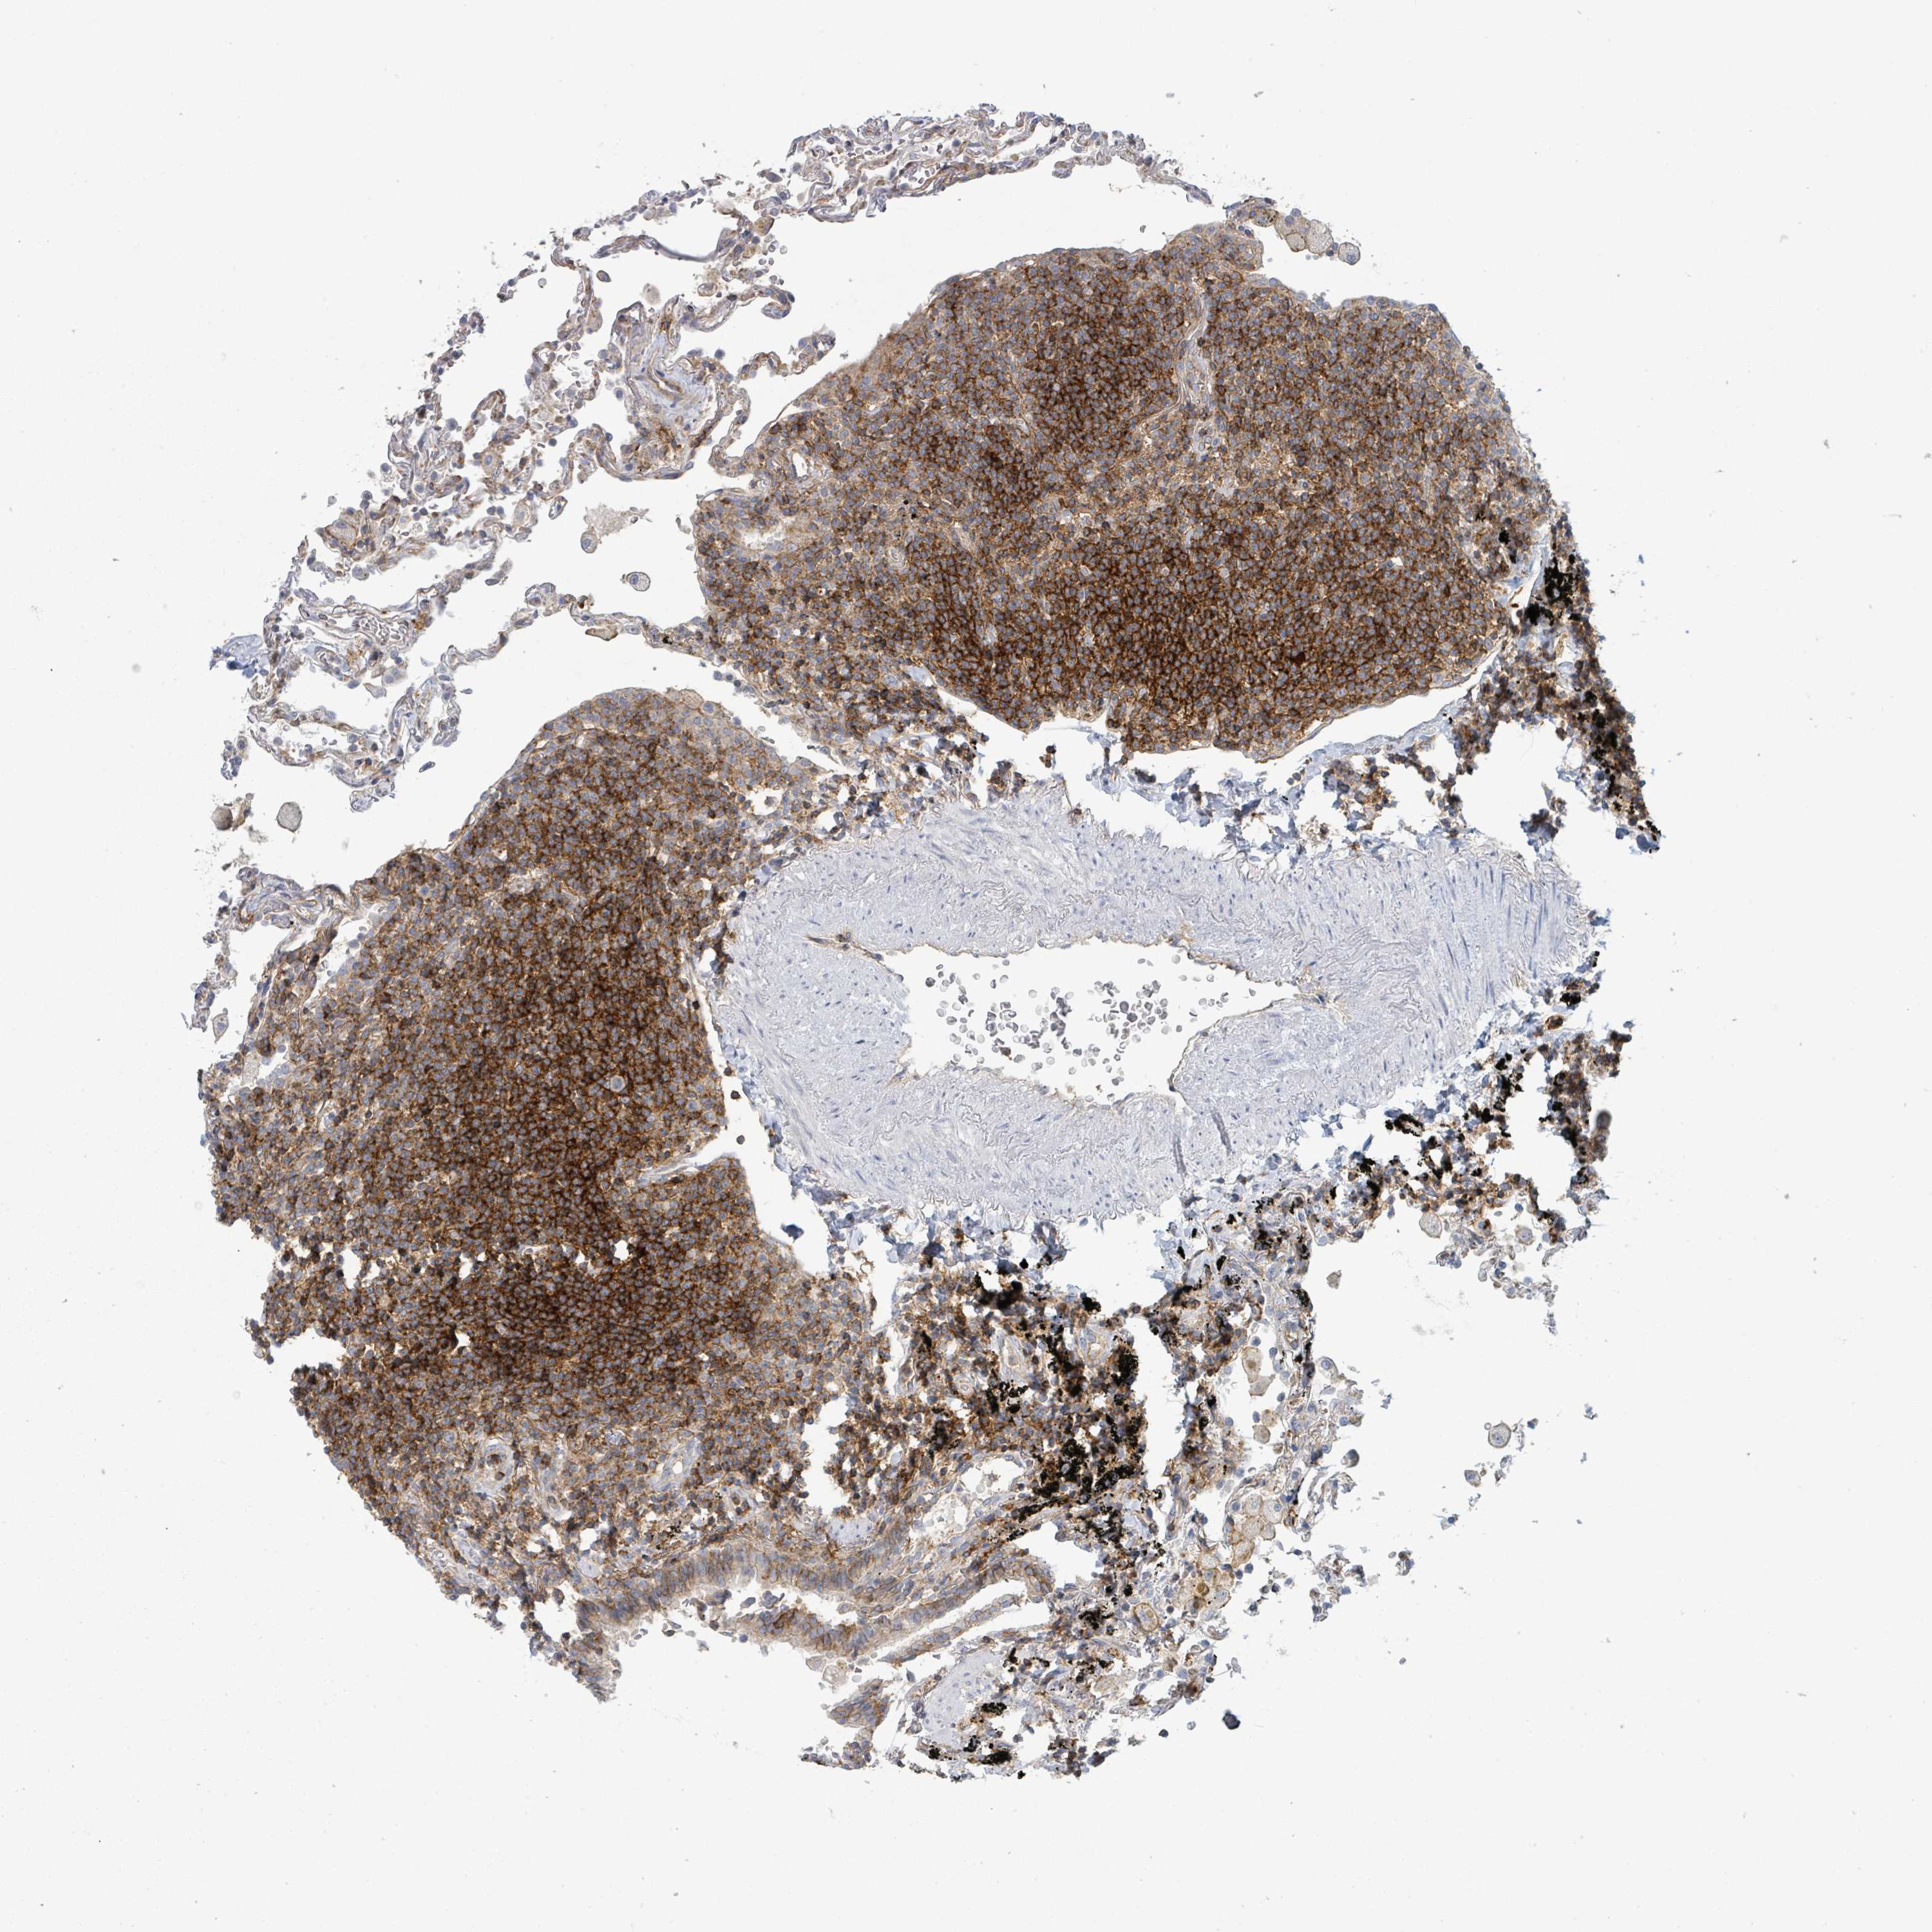

LYMPHOMA - Protein expressioni

A mouse-over function shows sample information and annotation data. Click on an image to view it in a full screen mode. Samples can be filtered based on level of antibody staining by selecting one or several of the following categories: high, medium, low and not detected. The assay and annotation is described here.

Antibody stainingi

Antibody staining in the annotated cell types in the current human tissue is reported as not detected, low, medium, or high, based on conventional immunohistochemistry profiling in selected tissues. This score is based on the combination of the staining intensity and fraction of stained cells.

Each image is clickable and will lead to virtual microscopy that enables deeper exploration of all samples and also displays staining intensity scores, fraction scores and subcellular localization as well as patient and tissue information for each sample.

Antibody CAB030007